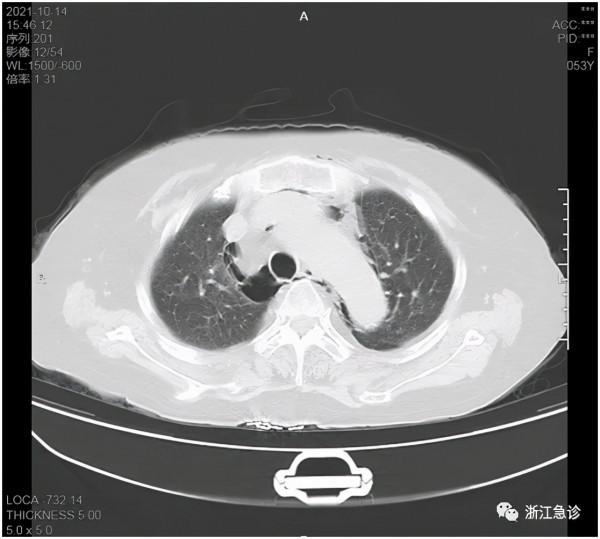

患者女性,53歲,1周前自己發現左側會陰面板紅腫,沒有引起重視,過了二天紅腫範圍增大,觸之有壓痛,活動後明顯,伴乏力,活動受限,有腹痛不適,無發熱,無腹瀉,無噁心嘔吐等不適。患者原有高血壓、糖尿病及肝血管瘤手術史。到了第三天,因為病灶擴大迅速,就到當地醫院就診,這時患者整個胸腹部面板出現瘀點瘀斑,胸部CT發現廣泛縱膈氣腫及左側腹膜後氣腫;還有兩肺炎症及左側胸腔少量積液,也就是說,病灶從左側腹股溝一直波及到腹、胸、縱膈及背部。這下嚇壞了當地醫師。因為從來沒有見過如此嚴重的病例,感到問題嚴重,就轉到縣級市人民醫院。當地人民醫院發現炎症很嚴重(血常規+超敏C反應蛋白:WBC 9.1+10^9/L,Hb 129g/L,PLT 135+10^9/L,CRP 330.83mg/L),同時已經出現呼吸衰竭的傾向,急轉來我院。急診又做了全腹部CT和頭顱CT,頭顱CT正常,腹壁下有廣泛的積氣積液,立即收住入急診ICU。